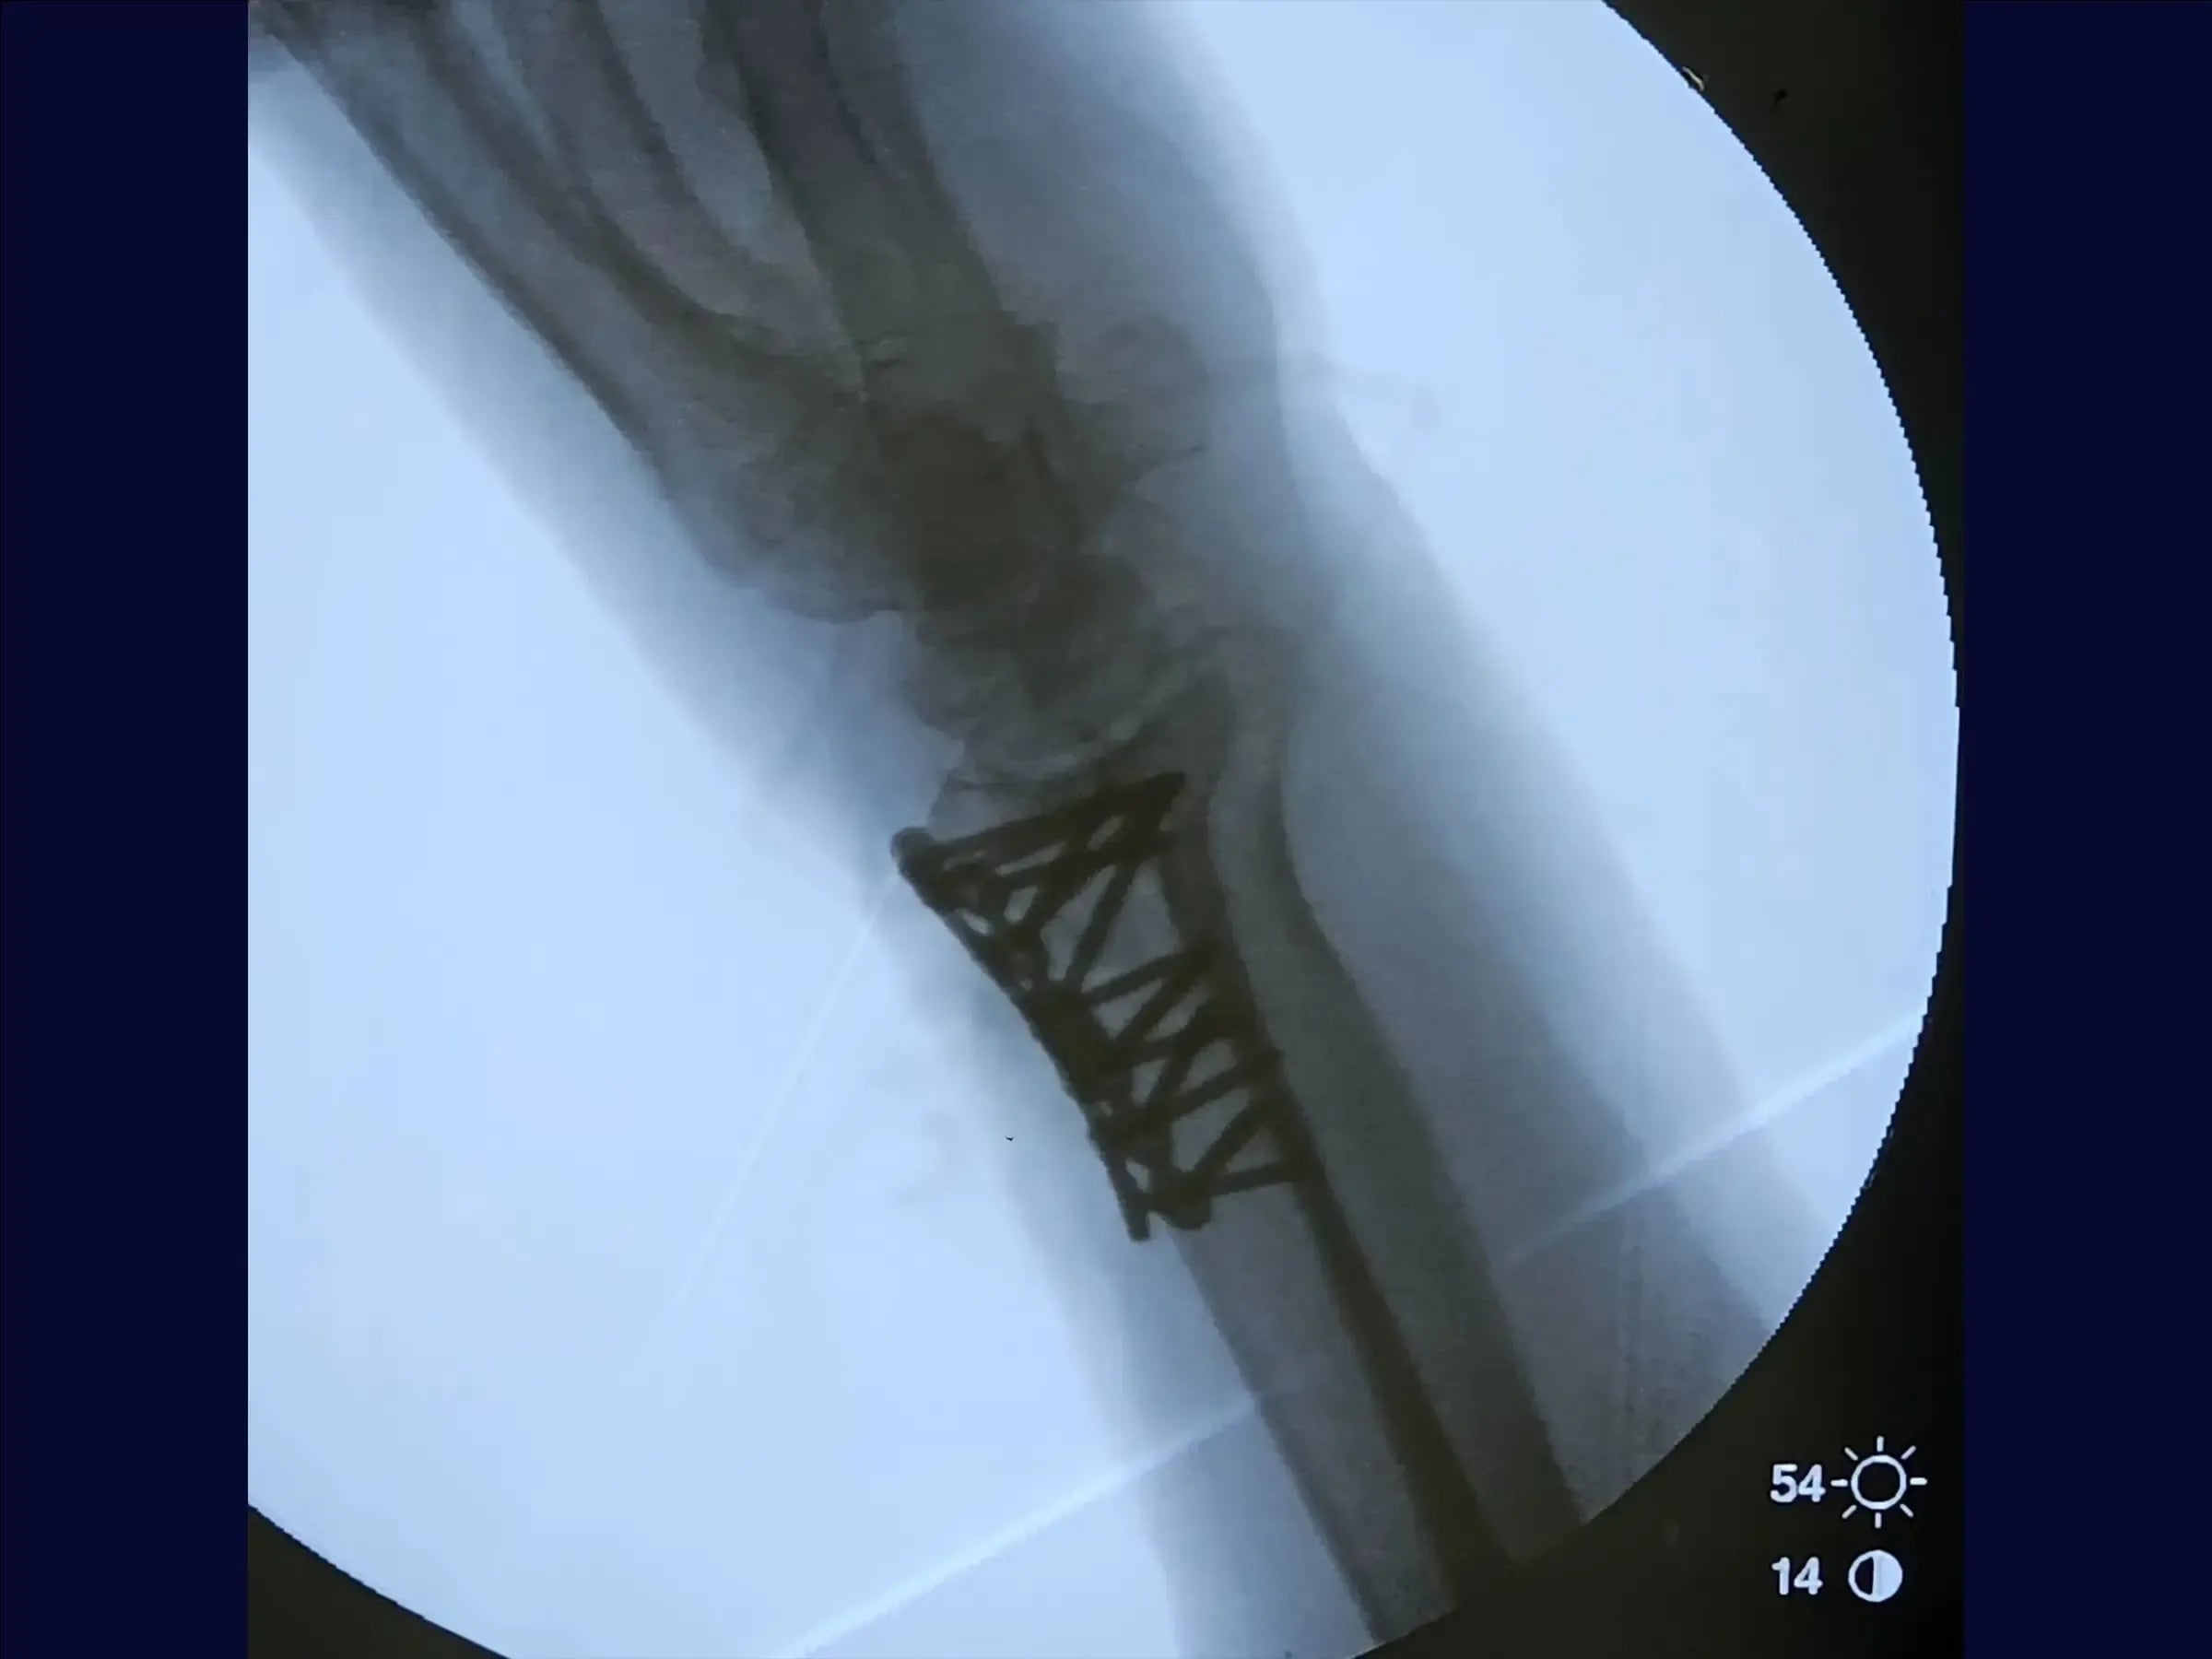

- Fixação e Verificações: Após a placa principal, o treinamento ensina a usar uma segunda placa de baixo perfil para fragmentos dorsais destacados, visando restaurar a região articular. São ensinadas verificações para assegurar que nenhum tendão esteja sob a placa e que os orifícios não violem a articulação.

- Fechamento e Resultados: As placas são posicionadas junto ao osso, garantindo tendões livres. O treinamento cobre a avaliação da redução em termos de comprimento radial, angulação e inclinação, e a liberação imediata da mobilidade em pacientes idosos no pós-operatório. O fechamento da pele encerra o procedimento.